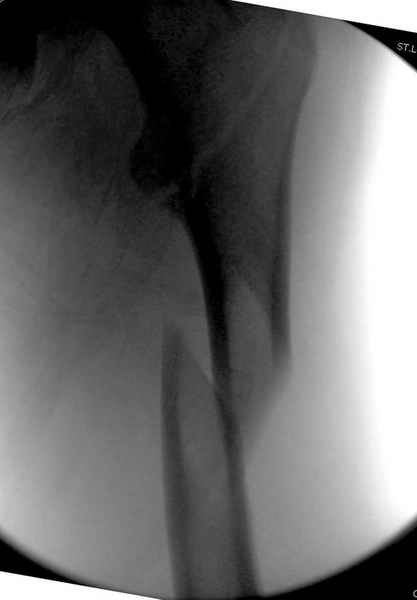

Второй случай тоже репозиция из малого доступа, больному 19 лет, множественные огнестрельные повреждениия конечностей, живота и черепа, правая конечность холодная, без пульсации. Ортопедический диагноз: огнестрельный перелом правого бедра. При срочной ангиографии повреждения сосудов не подтвердилось, конечность из-за ургентности состояния больного зафиксирована временным наружным фиксатором и больной оставлен на операционном столе для срочной лапаротомии хирургической службой.

Больной долго оставался нестабильным, только на 14 день удалось заменить на антеградный интромедуллярный штифт TFN (trochanteric femoral nail) SmithNephew. После неудачной попытки закрытой репозиции, несмотря на использование "joystick", проксимальный стержень от

наружного фиксатора, (перелом начал срастаться) репозицию провели из малого доступа, затем остальные этапы операции.

Случай был представлен из-за того, что больного оперировали после наружной фиксации и был риск инфекцирования через места проведения стержней (на снимках), прошло больше 3 месяцев, выписан из амбулаторной службы из-за отсутсвия надобности дальнейшего наблюдения.